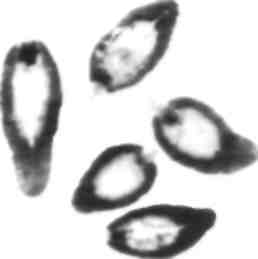

Идентификация

Макроскопическое исследование

Так как Dicrocoelium имеет менее 1.0 см в длину, четкую ланцетовидную форму и полупрозрачен, то представителей этого рода нельзя ошибочно принять за других трематод

Микроскопическое исследование

Кишечник простой, состоит из двух ветвей и напоминает камертон За вентральной присоской вместе лежат семенники, за которыми сразу же располагаются яичники. Шипов на кутикуле нет (по сравнению с Fasciola). Яйцо небольшое. 45 х 300 /нп. темно-коричневое и имеет крышечки, обычно с уплощенной стороной. Яйцо при выходе с фекалиями содержит мирацидий.